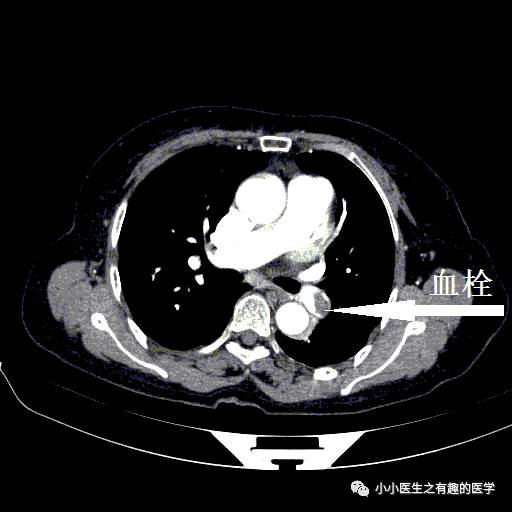

病例一:

女性,老年,胸痛伴气喘20余天。1周前出现双下肢浮肿。查体:双下肢足背浮肿。D-二聚体:5.10 ug/mL。心脏彩超:肺动脉收缩压RVSP:39mmHg。B超:双下肢深静脉血栓形成。

左肺动脉血栓。